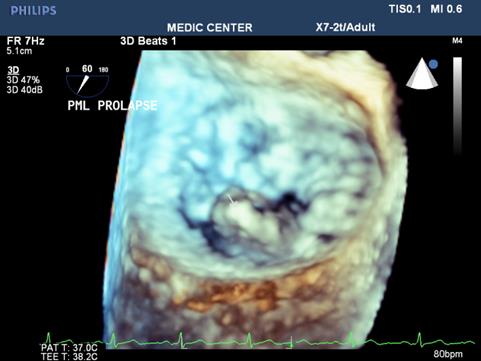

Among patients with mitral regurgitation, MVP accounts for the majority of our patients, fibroelastic disease and Barlow type of MVP were seen (Figures 18-21).

Figure 19. RT-3DTEE notes protruding PML viewed from LA side

Figure 20. Excentric jet MR due to Flail MV

Figure 21. Live 3D shows the severe MR